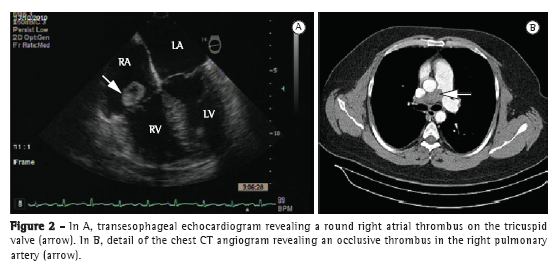

A 37-year-old man presented to the emergency room of the Hospital das Clínicas da Universidade Federal de Minas Gerais (HC-UFMG, Federal University of Minas Gerais Hospital das Clínicas), located in the city of Belo Horizonte, Brazil, with a two-day history of moderate dyspnea. Two years prior, the patient had had a similar episode, which was treated as bronchospasm. Six years prior, the patient had undergone left transtibial amputation because of popliteal artery occlusion. After one year of anticoagulation therapy (warfarin), he was diagnosed with muscular compression of the right popliteal artery, which was corrected surgically. At the time, factor VIII levels were found to be increased (200 IU/dL). The patient had a normal electrocardiogram. Physical examination revealed that the patient was alert, with an SpO2 of 90%, an HR of 72 bpm, and an arterial pressure of 150/100 mmHg. Cardiopulmonary examination was normal. A chest X-ray showed accentuation of the vascular markings on the left. A transthoracic echocardiogram (TTE) revealed a mobile thrombus (18 × 15 mm) attached to the posterior leaflet of the tricuspid valve and insinuating itself into the right ventricle (RV). Another thrombus (13 × 14 mm) was located in the inferior vena cava (IVC), diffuse right ventricular hypocontractility and impaired left ventricular diastolic relaxation having been observed. Lung scintigraphy (LS) revealed a homogeneous pattern of ventilation, markedly decreased right lung perfusion, and normal left lung perfusion (Figure 1). Although the patient had received anticoagulation therapy, he presented with persistent dyspnea and an SpO2 of 93%. A transesophageal echocardiogram revealed a large mobile thrombus located in the right atrium (RA) and projecting into the RV, as well as right ventricular dysfunction (Figure 2A). A chest CT angiogram revealed peripheral consolidations on the right and occlusion of the right pulmonary artery (2.9 cm), as well as filling defects in the upper lobe branch, middle lobe branch, lower lobe branch, segmental branch, and subsegmental branch, together with thrombi in six subsegmental branches of the left lower lobe (Figure 2B). A follow-up TTE, performed 17 days later, revealed an ejection fraction of 0.79, a dilated, hypokinetic RV, a pulmonary artery systolic pressure of 39 mmHg, and persistence of the thrombus in the RA. In that phase, oral anticoagulation therapy was maintained, in accordance with a decision made by the team of physicians, the patient, and his family. The patient was discharged on warfarin and was referred to the pulmonology department. He was readmitted in the following month because of worsening dyspnea. A second LS was performed, revealing a pattern that was similar to that which was revealed by the first. A TTE revealed that the intra-atrial thrombus and the thrombus in the IVC persisted, although they were smaller than the previous TTE had shown it to be. Because of those changes and symptoms, thrombolysis (alteplase, 100 mg in 2 h) was performed in the ICU. The procedure was uneventful. A transesophageal echocardiogram performed five days after the thrombolysis procedure showed that the thrombus in the RA had disappeared completely and that the thrombus (17 mm) in the IVC persisted. A follow-up LS performed 72 h later revealed no signs of lung reperfusion. His dyspnea having improved, the patient was discharged on warfarin and was referred to the HC-UFMG Department of Pulmonology for outpatient follow-up treatment.